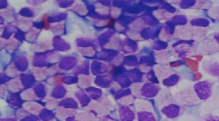

You note round cells in the liver. What does this indicate

Neoplastic metastasis to liver

Is this a normal hepatocyte

No - bile duct carcinoma

Round cells